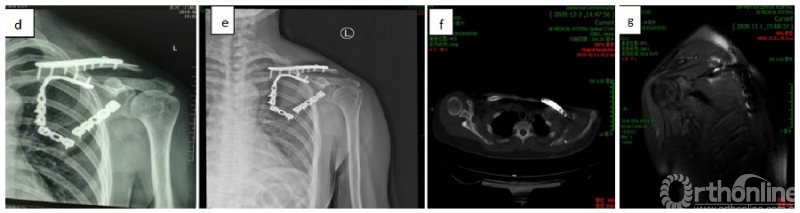

术前术后影像学资料

注:图a为术前X线片(2018.12.12),可见锁骨及肩胛骨骨折;图b为术前CT轴位肩锁关节平面(2018.12.12),可见肩锁关节脱位;图c为术后X线片(2018.12.29),左锁骨及左肩胛骨固定术后。